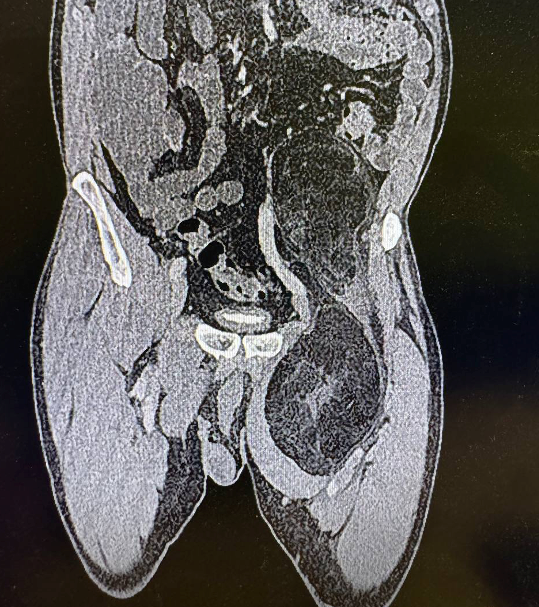

МРТ от 30.12.2025: Крупное объемное образование полости таза, левой паховой области и в/3 бедра, с преимущественным содержанием в структуре жировой ткани.

КТ с в/в контрастированием + режим ангиографии